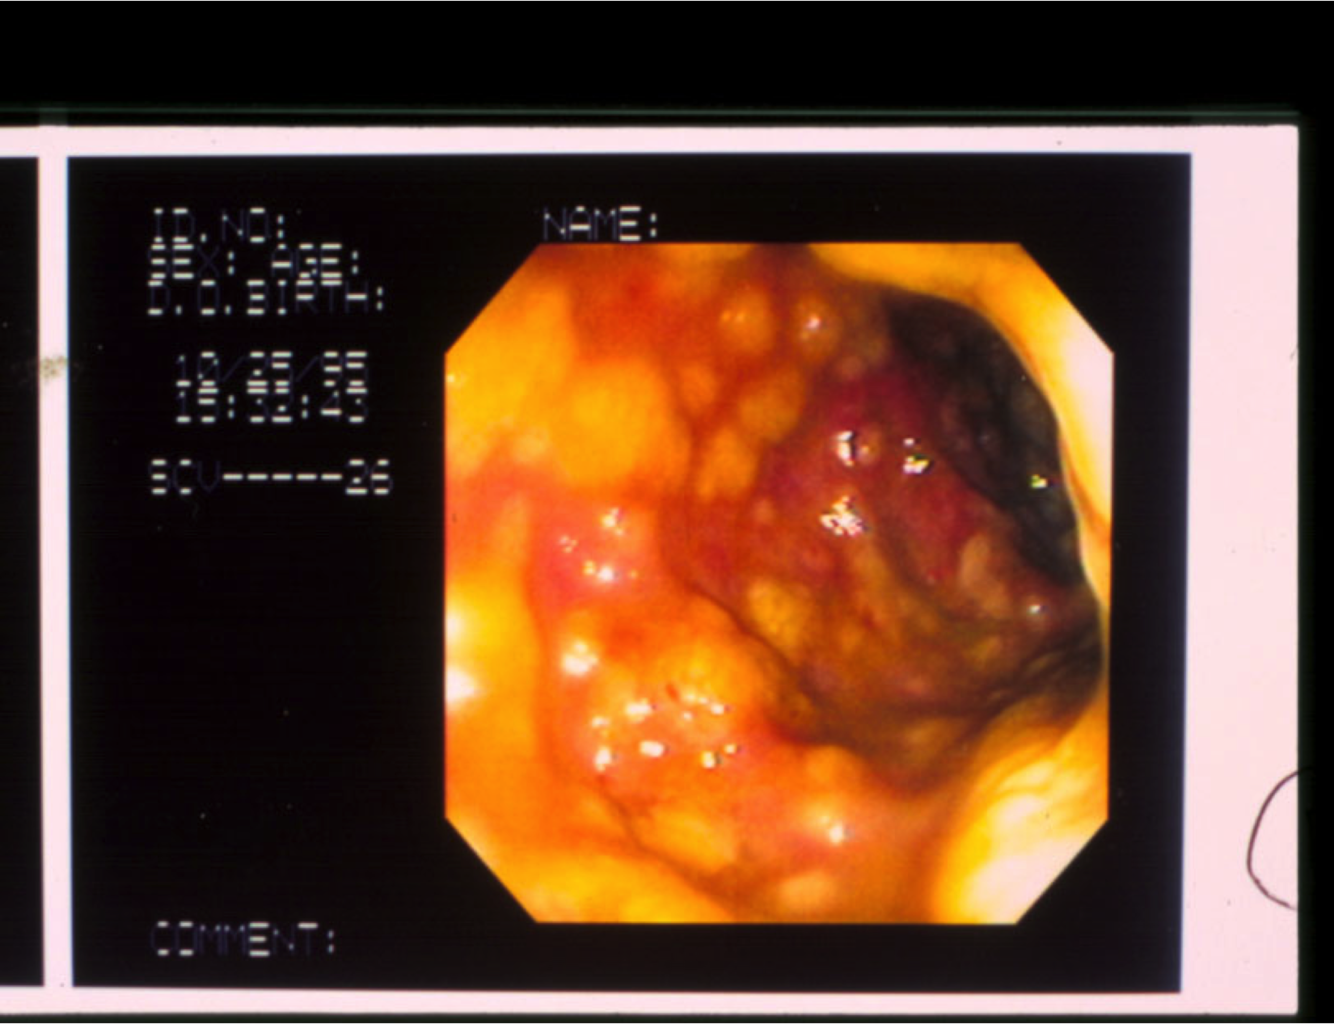

What disease? features?

Crohn’s.

characteristic endoscopic features of nodularity, ulceration, exudate and luminal narrowing